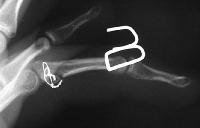

Clinical Example: Hemicondylar Hamate Replacement Arthroplasty for Proximal Interphalangeal Joint Fracture Dislocation

20 year old on the track to pro baseball, with a story that he jammed his non dominant left ring finger in training 6 weeks ago. Still playing, but it hurts when hit on the end or when hyperextended.

PIP is swollen and a bit tender. E/F 20/80, probably a few degrees of radial angulation.

Xrays show an apparently healed PIP fracture dislocation with dorsal subluxation - but concentric tracking of the abnormal palmar articulation.